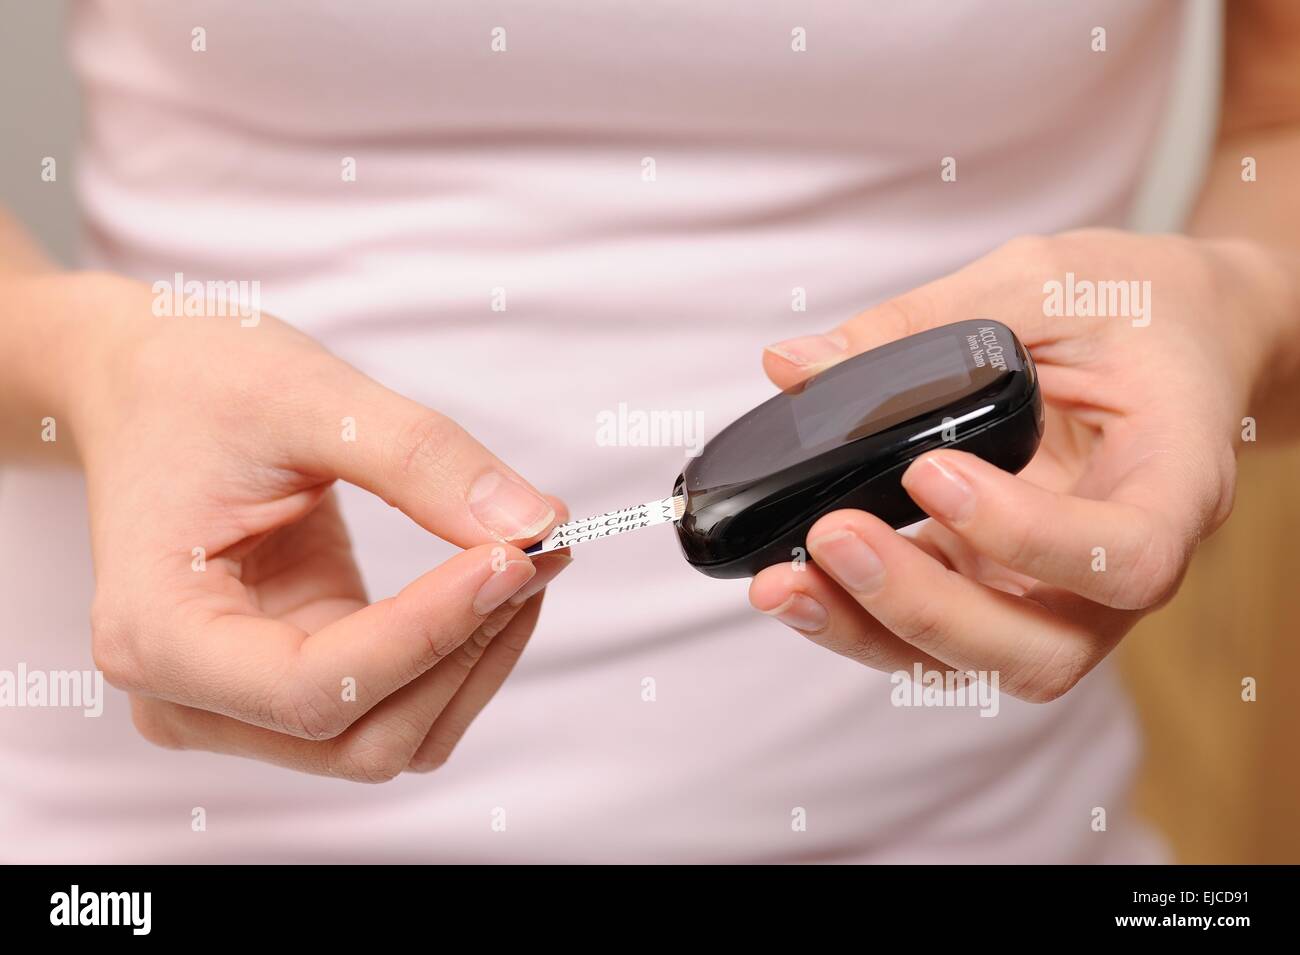

Accu chek avia nano Foto Stockhttps://www.alamy.it/image-license-details/?v=1https://www.alamy.it/foto-immagine-accu-chek-avia-nano-80179165.html

Accu chek avia nano Foto Stockhttps://www.alamy.it/image-license-details/?v=1https://www.alamy.it/foto-immagine-accu-chek-avia-nano-80179165.htmlRMEJCD9H–Accu chek avia nano

Accu chek avia nano Foto Stockhttps://www.alamy.it/image-license-details/?v=1https://www.alamy.it/foto-immagine-accu-chek-avia-nano-80179164.html

Accu chek avia nano Foto Stockhttps://www.alamy.it/image-license-details/?v=1https://www.alamy.it/foto-immagine-accu-chek-avia-nano-80179164.htmlRMEJCD9G–Accu chek avia nano

Accu chek avia nano Foto Stockhttps://www.alamy.it/image-license-details/?v=1https://www.alamy.it/foto-immagine-accu-chek-avia-nano-80179136.html

Accu chek avia nano Foto Stockhttps://www.alamy.it/image-license-details/?v=1https://www.alamy.it/foto-immagine-accu-chek-avia-nano-80179136.htmlRMEJCD8G–Accu chek avia nano

Accu chek avia nano Foto Stockhttps://www.alamy.it/image-license-details/?v=1https://www.alamy.it/foto-immagine-accu-chek-avia-nano-80179160.html

Accu chek avia nano Foto Stockhttps://www.alamy.it/image-license-details/?v=1https://www.alamy.it/foto-immagine-accu-chek-avia-nano-80179160.htmlRMEJCD9C–Accu chek avia nano

Accu chek avia nano Foto Stockhttps://www.alamy.it/image-license-details/?v=1https://www.alamy.it/foto-immagine-accu-chek-avia-nano-80179161.html

Accu chek avia nano Foto Stockhttps://www.alamy.it/image-license-details/?v=1https://www.alamy.it/foto-immagine-accu-chek-avia-nano-80179161.htmlRMEJCD9D–Accu chek avia nano

Accu chek avia nano Foto Stockhttps://www.alamy.it/image-license-details/?v=1https://www.alamy.it/foto-immagine-accu-chek-avia-nano-80179140.html

Accu chek avia nano Foto Stockhttps://www.alamy.it/image-license-details/?v=1https://www.alamy.it/foto-immagine-accu-chek-avia-nano-80179140.htmlRMEJCD8M–Accu chek avia nano

Accu chek avia nano Foto Stockhttps://www.alamy.it/image-license-details/?v=1https://www.alamy.it/foto-immagine-accu-chek-avia-nano-80179152.html

Accu chek avia nano Foto Stockhttps://www.alamy.it/image-license-details/?v=1https://www.alamy.it/foto-immagine-accu-chek-avia-nano-80179152.htmlRMEJCD94–Accu chek avia nano

Accu chek avia nano Foto Stockhttps://www.alamy.it/image-license-details/?v=1https://www.alamy.it/foto-immagine-accu-chek-avia-nano-80179149.html

Accu chek avia nano Foto Stockhttps://www.alamy.it/image-license-details/?v=1https://www.alamy.it/foto-immagine-accu-chek-avia-nano-80179149.htmlRMEJCD91–Accu chek avia nano